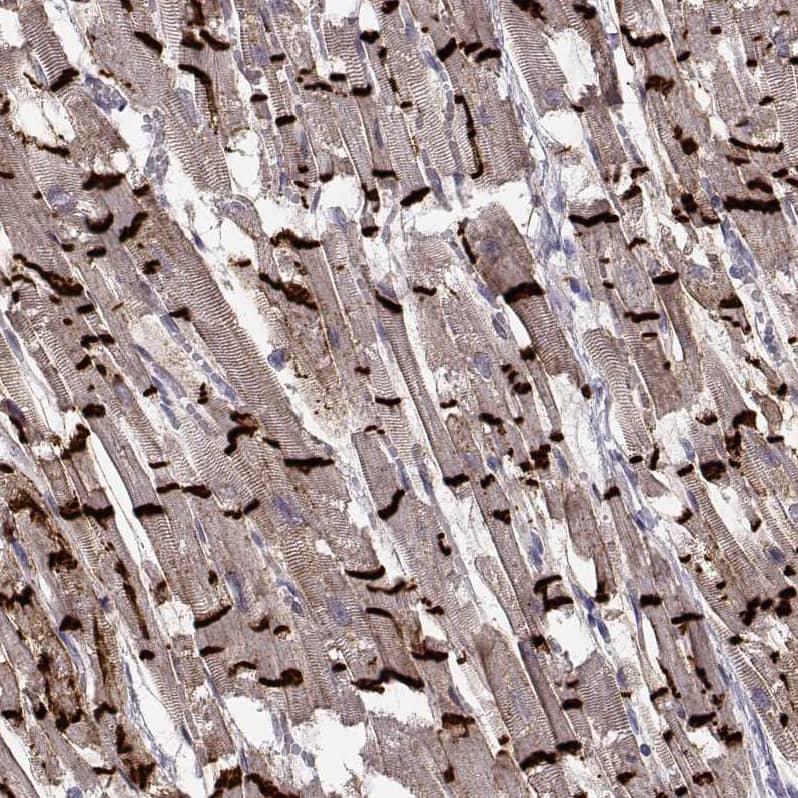

Orthogonal Strategies: Analysis in human heart muscle and skin tissues using NBP3-44495 antibody. Corresponding N-Cadherin RNA-seq data are presented for the same tissues.

Staining of human heart muscle shows strong positivity in the intercalated discs of cardiomyocytes.